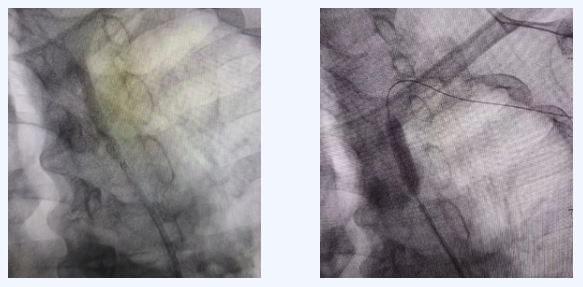

为明确诊断并制定治疗方案,神经内科与介入科医生团队迅速开展联合会诊,一致认为介入治疗是首选方案。随后,由独建库主任在DSA(数字减影血管造影)引导下,成功为患者实施了介入手术。

CTADSA(血管造影):可清晰显示血管狭窄的位置和程度,是诊断的金标准。

介入治疗

目前临床上常用的微创方法。医生通过股动脉穿刺,将球囊或支架送至狭窄处,扩张并支撑血管,恢复血流通畅。该方法创伤小、恢复相对较快。